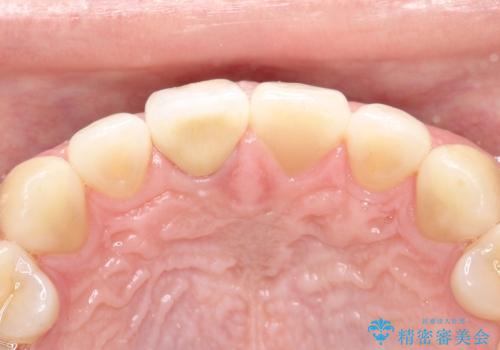

【前歯の被せ物】オールセラミッククラウン(エクセレント)

- 空隙歯列と前歯の変色を主訴に来院されました。

空隙歯列を矯正にて改善した後に歯冠修復を行なっております。

上顎前歯は根管治療後にオールセラミッククラウン(エクセレント)で修復を行なっております。